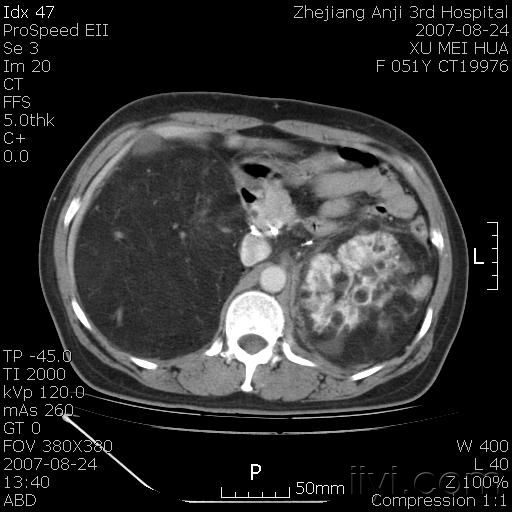

以下是引用还珠格格在2007-8-27 10:19:00的发言:[br]双侧肾脏形态失常,可见巨大的以低密度脂肪为主的混合性肿块,占据中下腹,残留的肾组织轻度强化,增强后肿块内实质部分呈峰窝状强化,低密度区无强化。另左侧肾盂轻度积水。根据病史 考虑 双肾血管平滑肌脂肪瘤可能性大。[br] 鉴别诊断 1、脂肪瘤,境界清楚,肿块内完全是脂肪,几乎没有软组织成分; 2、畸胎瘤:罕见,除有软组织成分外,另一特征是有钙化或骨化影组织。